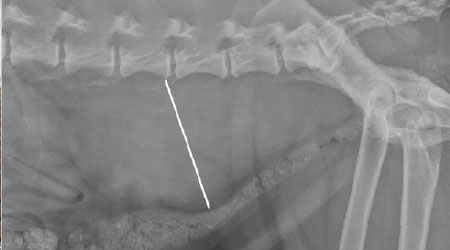

Canine Splenic Hemangiosarcoma

Canine Splenic Hemangiosarcoma By Beth Overley-Adamson | DVM, DACVIM (Oncology) Hemangiosarcoma (HSA) is a highly aggressive tumor that arises from the cells that make up the blood vessels. These cells undergo a genomic alteration from normal to malignant that allows…